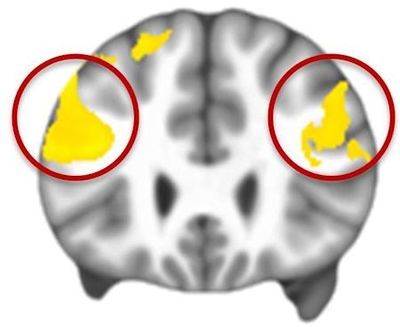

They found that in the control group, the prefrontal cortex worked hard to modulate the emotional response that originated in the limbic system - an evolutionarily old part of the brain associated with basic emotions and needs. This confirmed what other research had shown.

The brain scans of people with autism were different. "The prefrontal cortex did not come online to the same extent," Dichter said.

"It was as though the brain region that's needed to work hard to regulate emotional responses couldn't activate to the same degree as it did in people without autism. This limited activation of the prefrontal cortex, not surprisingly, resulted in less modulation of the limbic regions."

Thus, when faced with emotional situations, people with autism do not use their prefrontal cortices to regulate emotions to the same extent as people without autism. This in turn may lead to the "associated symptoms," such as anxiety, tantrums, and irritability, which can be pervasive.